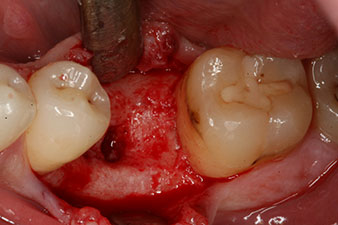

El torque en el momento de la carga mecánica fue de 43 Ncm. Asimismo, después de atornillar un poste de medición especial adaptado al sistema de implante (SmartPeg), el valor ISQ se determinó con la sonda del módulo Osstell ISQ de W&H.

Este módulo Osstell ISQ que se encuentra disponible como accesorio para la unidad Implantmed de W&H y se acopla al motor de implantes (véase figura 11). El valor ISQ adimensional fue de 64 justo en el momento de la inserción en la dirección bucovestibular y de 68 en la dirección mesiodistal (valor máximo = 100).

Este habría permitido una cicatrización abierta o incluso un tratamiento inmediato. Sin embargo, como no se disponía de suficiente hueso en la parte crestal del implante, el área se aumentó con las virutas óseas recopiladas durante la preparación del lecho del implante y se suturó para que no penetrara saliva.